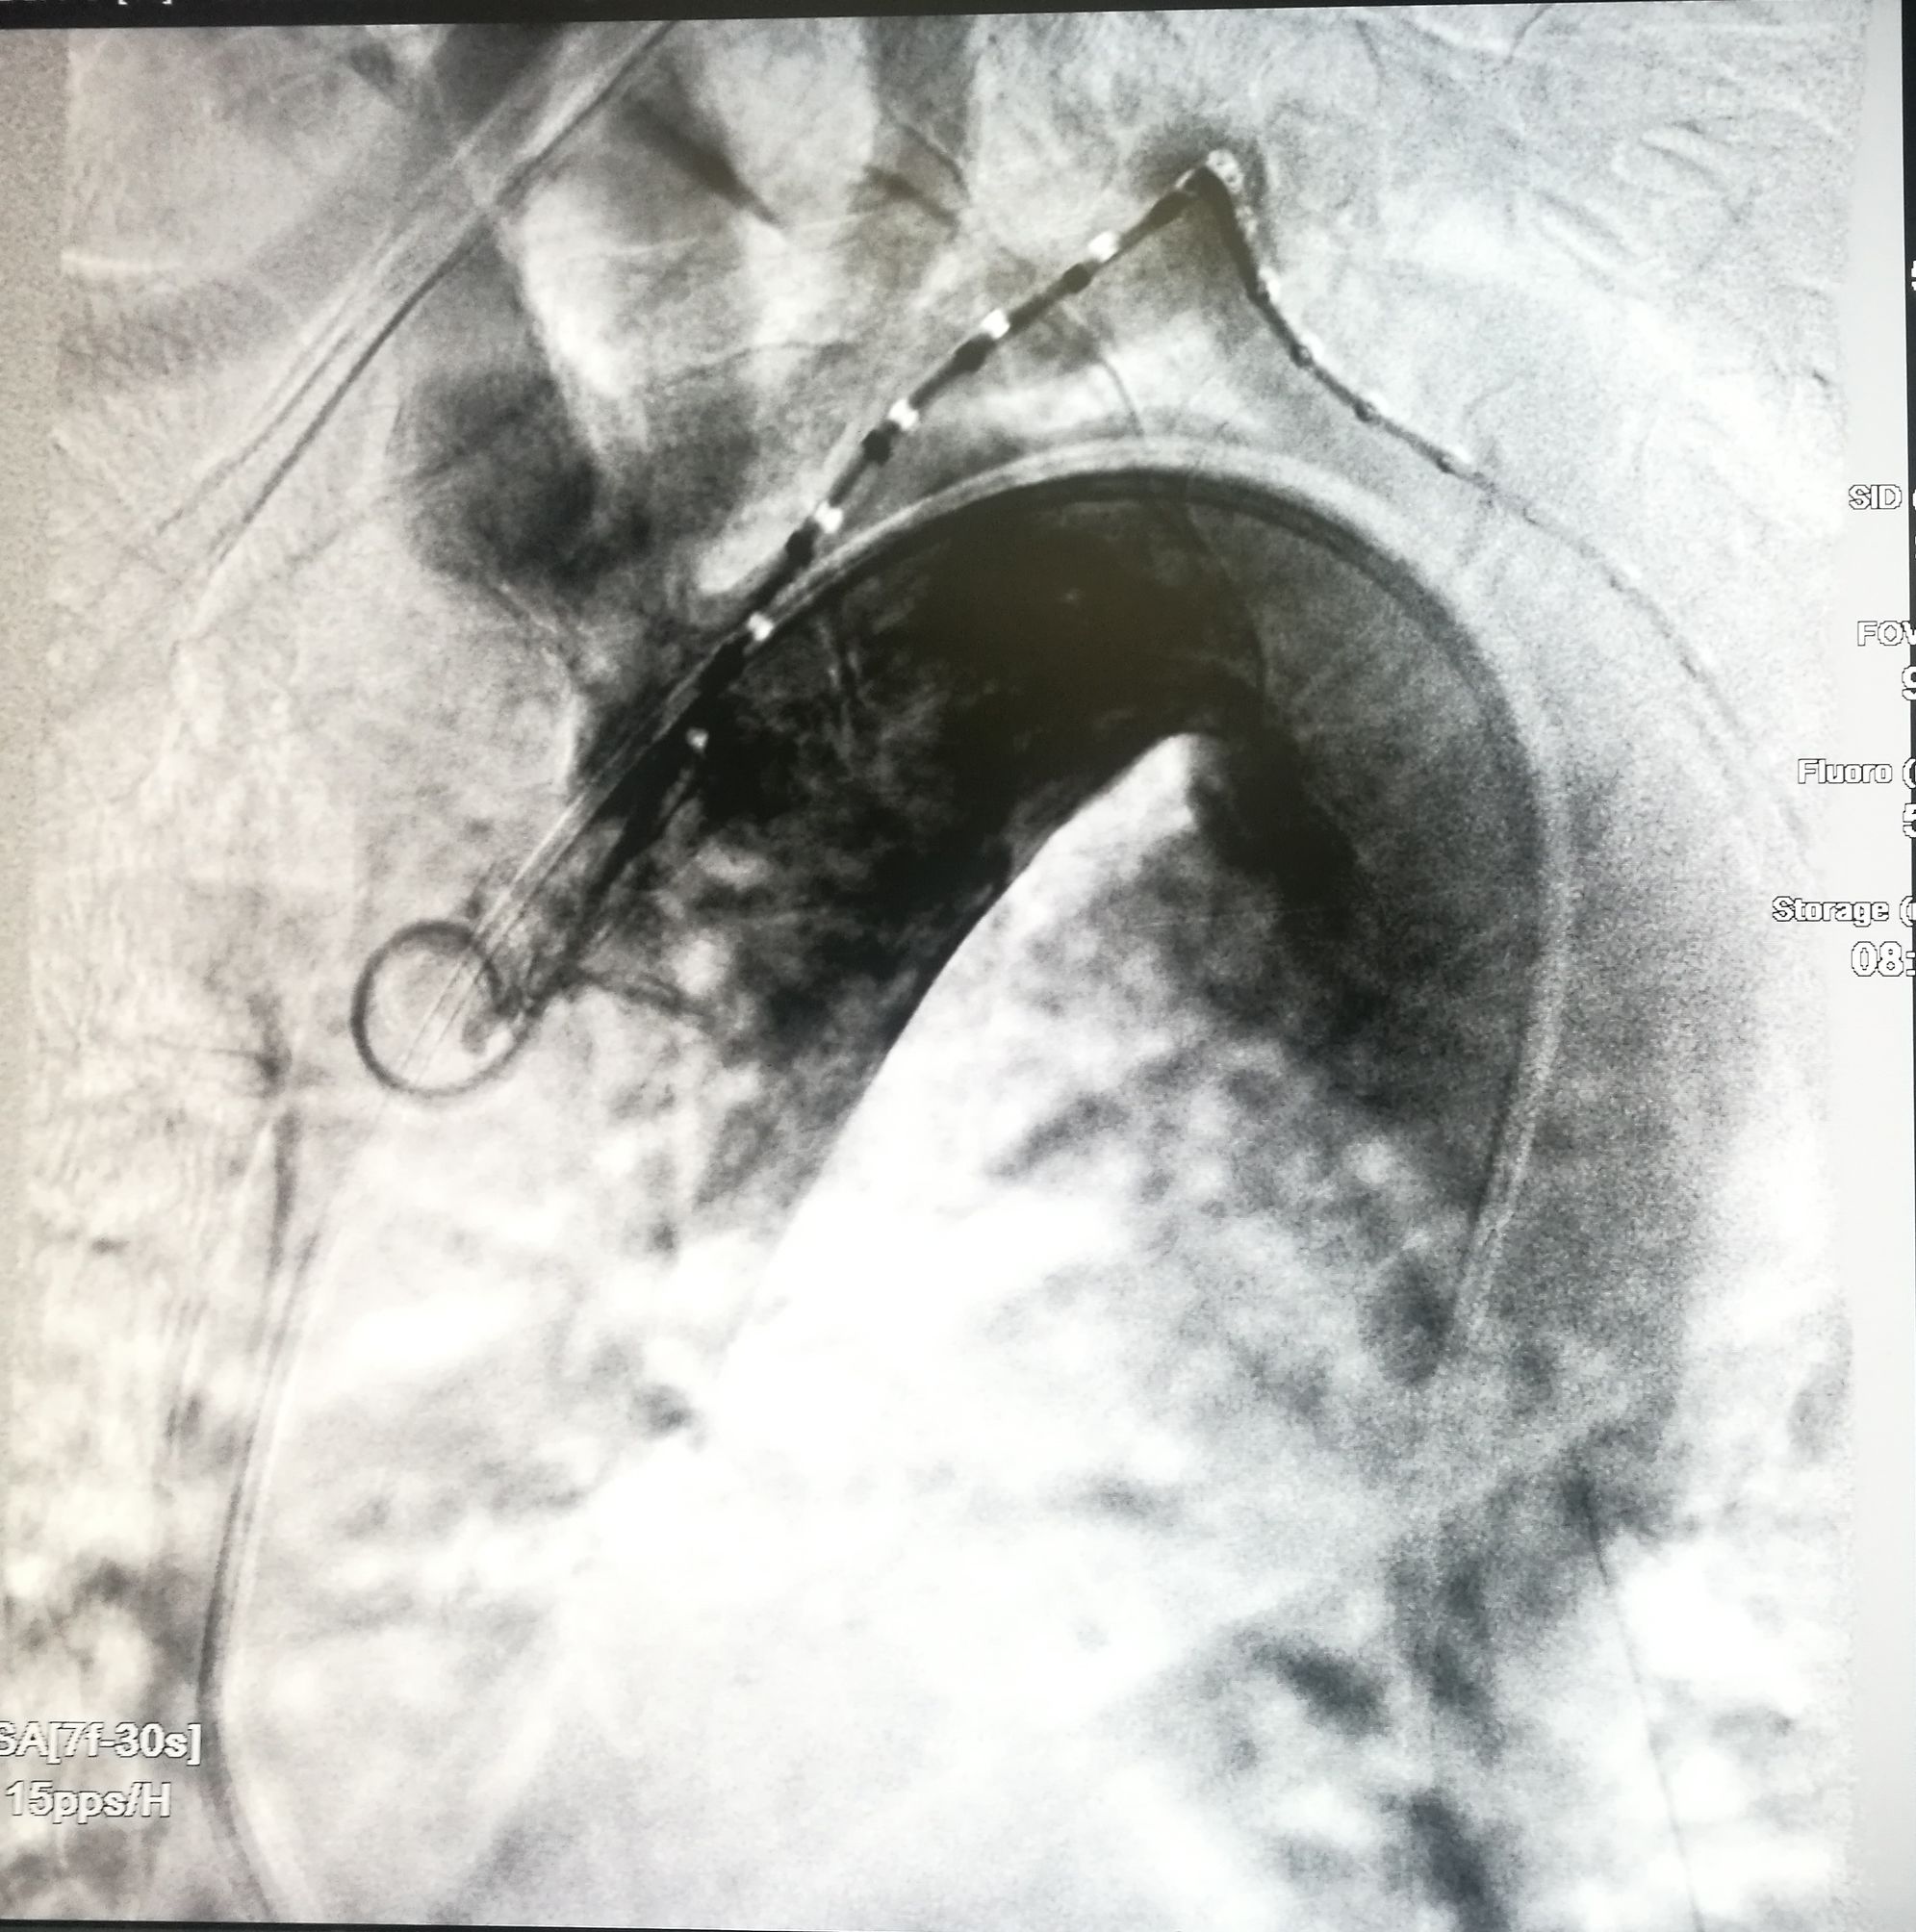

手术在局麻下进行,经右股动脉穿刺置管到升主,经左桡动脉穿刺植入金标猪尾导管,造影,为确认真假腔,加做右前斜位造影,确认股动脉导管在真腔内,测量后植入覆膜支架。由于扭曲严重(腹主,膈肌附近,弓降),支架最初并未贴服大湾侧,支架送过锁骨下动脉后适当回撤,请拉释放导丝,此时支架整体向大弯侧轻微移动,考虑应力已经得到缓解。完全释放支架,定位良好,封堵完全无内漏。

尽管有加硬导丝,但从二维影像上看,支架并未贴着大弯侧走行